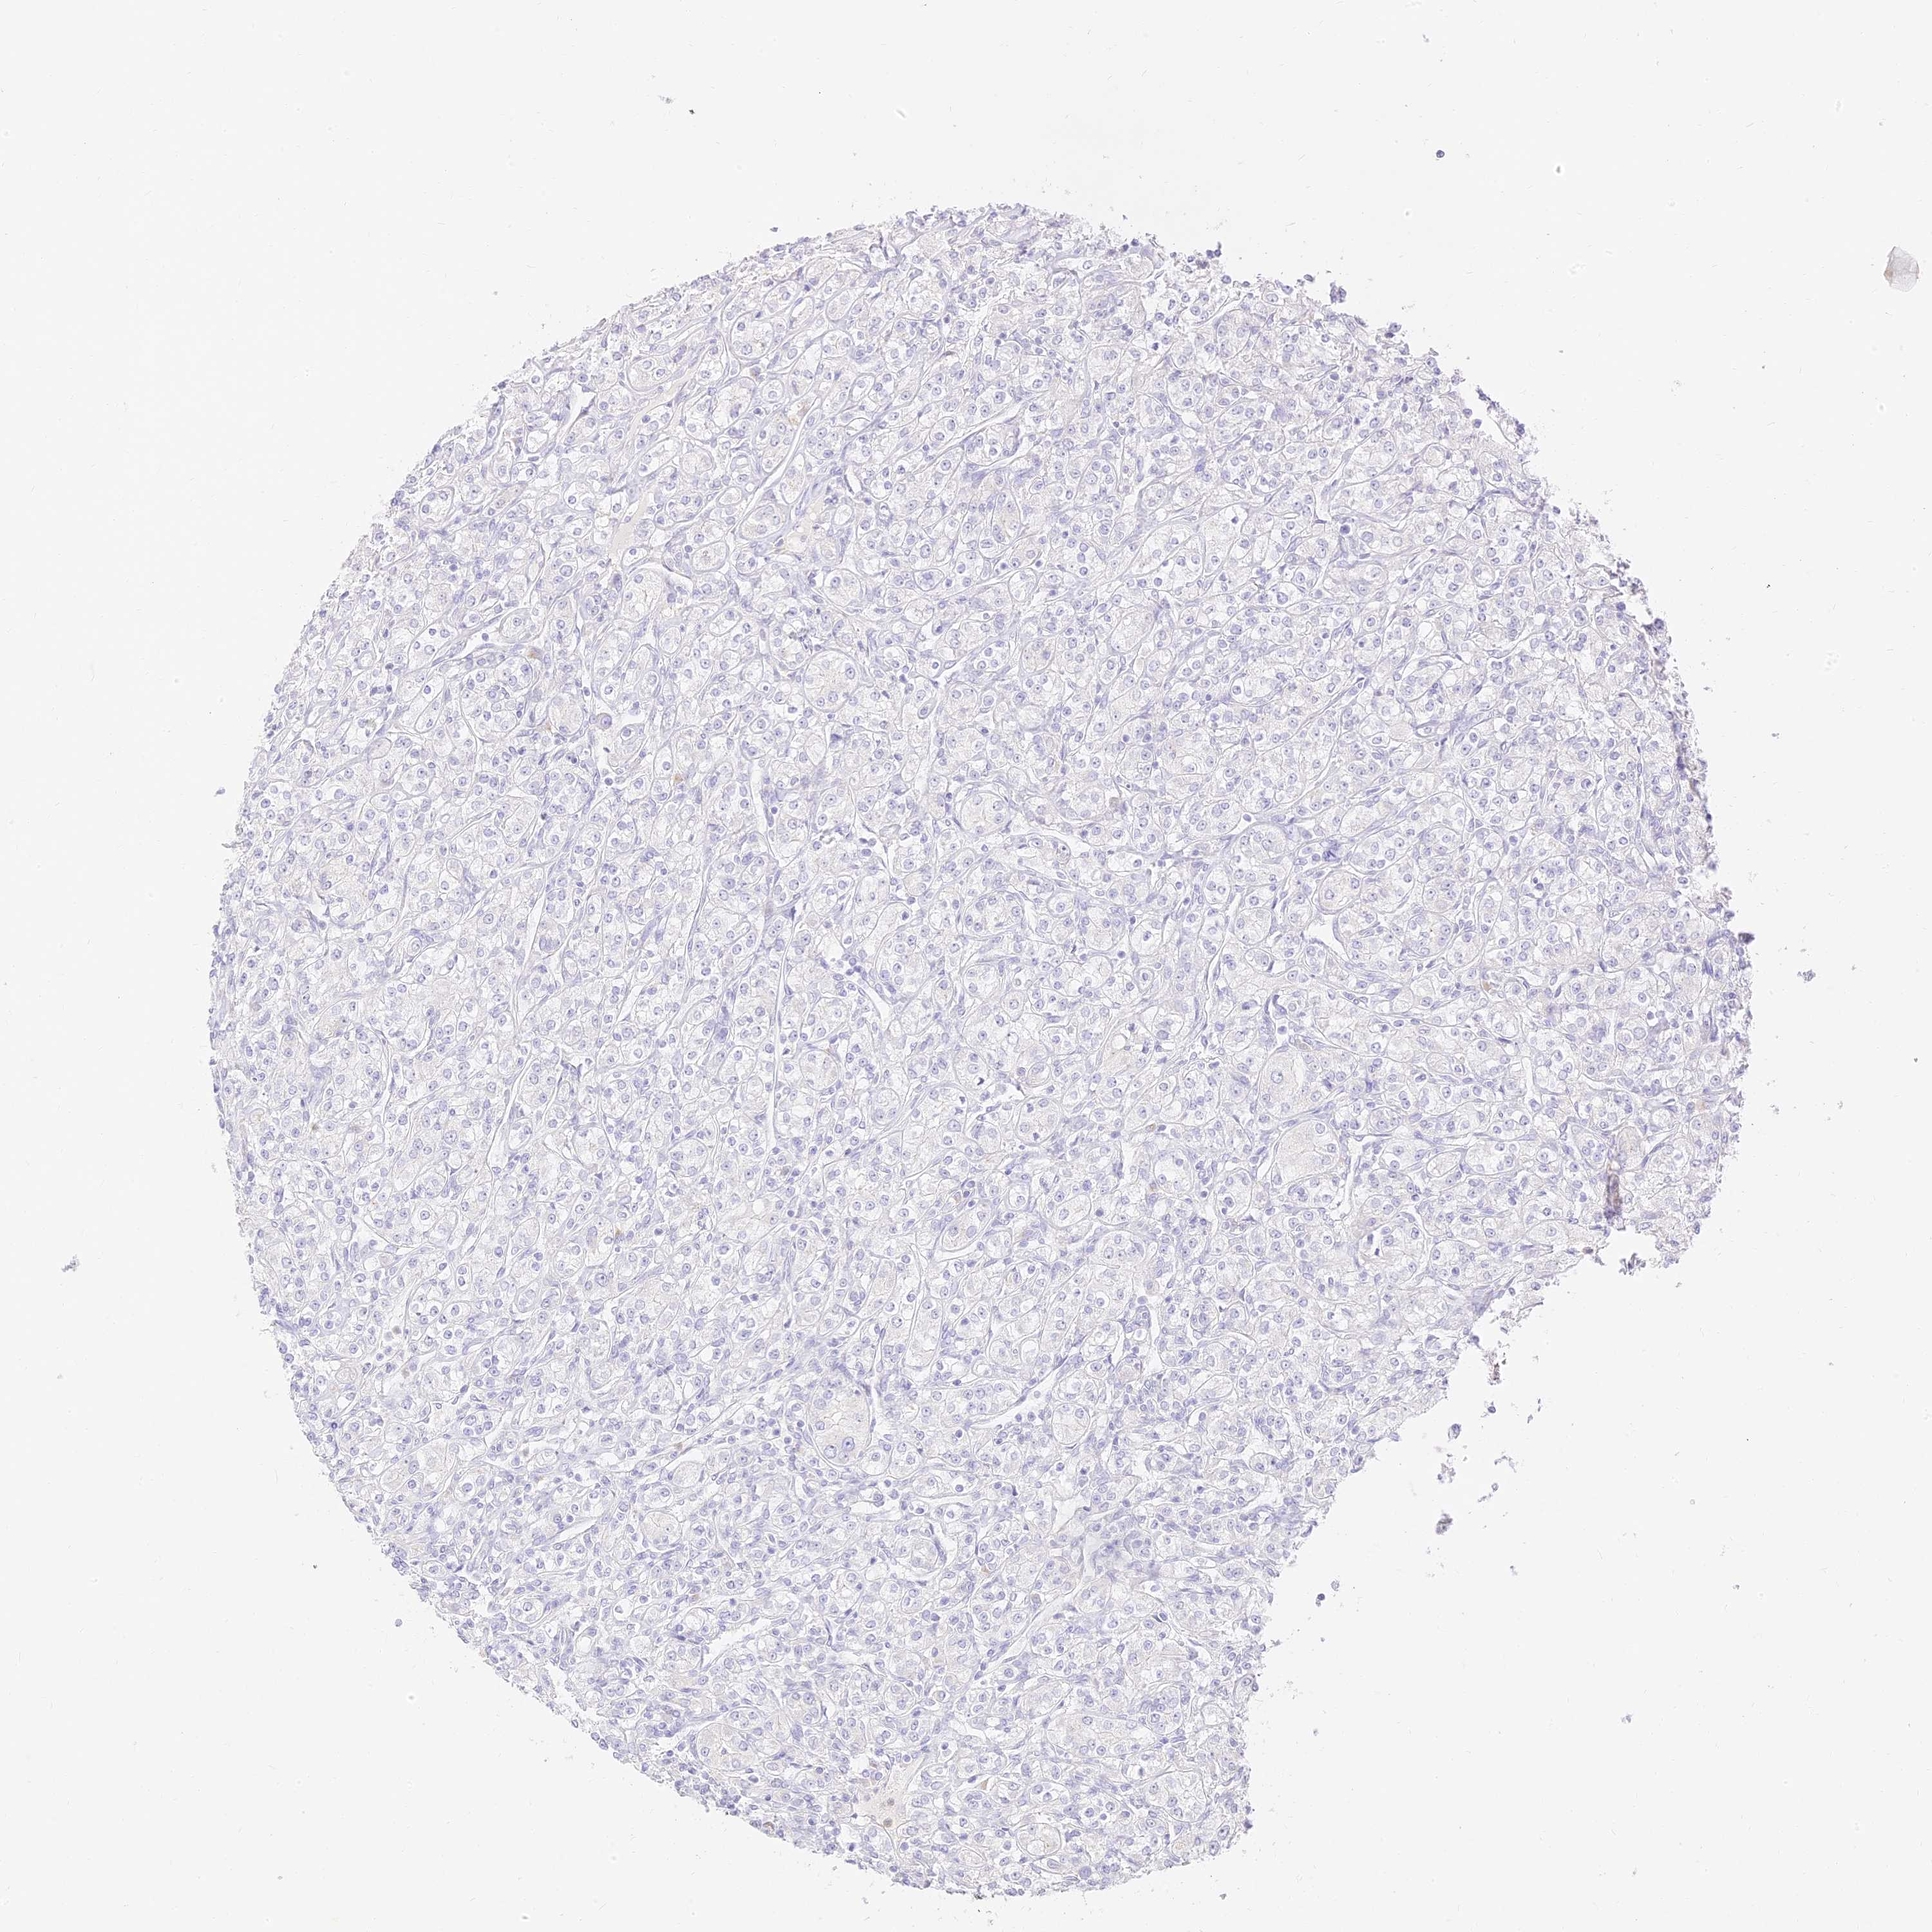

KIDNEY RENAL PAPILLARY CELL CARCINOMA (TCGA) - Interactive survival scatter ploti

The Survival Scatter plot shows the clinical status (i.e. dead or alive) for all individuals in the patient cohort, based on the same data that underlies the corresponding Kaplan-Meier plots. Patients that are alive at last time for follow-up are shown in blue and patients who have died during the study are shown in red.

The x-axis shows the expression levels (FPKM) of the investigated gene in the tumor tissue at the time of diagnosis. The y-axis shows the follow-up time after diagnosis (years). Both axes are complimented with kernel density curves demonstrating the data density over the axes. The top density plot shows the expression levels (FPKM) distribution among dead (red) and alive patients (blue). The right density plot shows the data density of the survived years of dead patients with high and low expression levels respectively, stratified using the cutoff indicated by the vertical dashed line through the Survival Scatter plot. This cutoff is automatically defined based on the FPKM cutoff that minimizes the p-score. The cutoff can be changed by dragging the vertical line or by entering a cutoff value in the square labeled "Current cut-off".

Under the Survival Scatter plot the p-score landscape (black curve; left axis) is shown together with dead median separation (red curve; right axis). Dead median separation is the difference in median mRNA expression between patients who have died with high and low expression, respectively. It is calculated as follows: median FPKM expression of dead patients with high expression - median FPKM expression of dead patients with low expression. This is intended to aid the user in visually exploring custom cutoffs and the associated p-scores and dead median separation.

Individual patient data is displayed and can be filtered by clicking on one or more of the category buttons on the top of the page. Categories describing expression level and patient information include: high, low, alive, dead, female, male and tumor stages. The scale of the x-axis can be toggled between linear and log-scale by clicking on the "x log" button. Mouse-over function shows TCGA ID, patient information and mRNA expression (FPKM) for each patient.

& Survival analysisi

Kaplan-Meier plots summarize results from analysis of correlation between mRNA expression level and patient survival. Patients were divided based on level of expression into one of the two groups "low" (under cut off) or "high" (over cut off). X-axis shows time for survival (years) and y-axis shows the probability of survival, where 1.0 corresponds to 100 percent.

SEC13 is not prognostic in Kidney Renal Papillary Cell Carcinoma (TCGA)